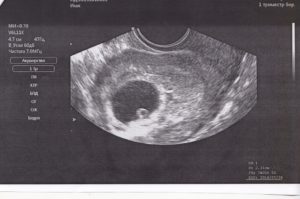

Во время первого ультразвука специалист-диагност выявляет образование с повышенной эхогенностью. Так выглядит плодное яйцо, величина которого позволяет судить о сроке данной беременности.

Ещё на мониторе будут видны желточный мешок, расположение зародыша, толщина внутреннего слоя матки. Врачи убедятся в отсутствии у женщины воспалений, полипов, кист и опухолей. Расшифровывать данные должен только профильный диагност.

Во время первого УЗИ обнаруживаются:

- круглое или каплевидное образование с низкой эхогенностью размером 3-5 мм. Его размер определяет срок;

- тонкая оболочка вокруг развивающегося ребёнка;

- жёлтое тело – оно вырабатывает прогестерон, способствующий сохранению плода.